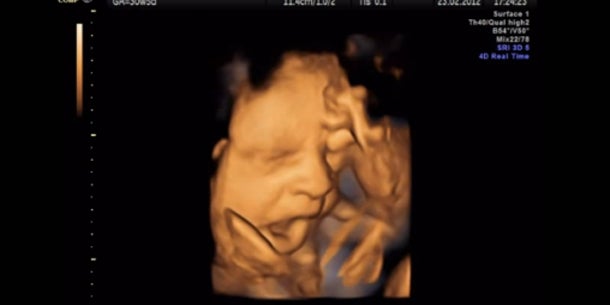

Dass Babys bereits im Mutterleib gähnen, konnte zum ersten Mal auf Bilder gebannt werden.

Es war bereits bekannt, dass Föten ihren Mund öffnen und schließen, trotzdem wollten die Wissenschaftler der Diskussion um das pränatale Gähnen ein Ende setzen und rückten mit einem hochauflösenden Ultraschall einem schwangeren Bauch auf die Pelle. Daraus enstanden süße Bilder.

Warum die Unbgeborenen gähnen? Es soll jedenfalls nicht aufgrund von Müdigkeit oder Langeweile sein. „Im Gegensatz zu uns gähnen Föten nicht weil sie müde sind,“ so Studienleiterin Dr. Nadja Reissland von der University of Durham. Nein, die Häufigkeit des Gähnens weist vielmehr auf die Reife des Gehirns hin.